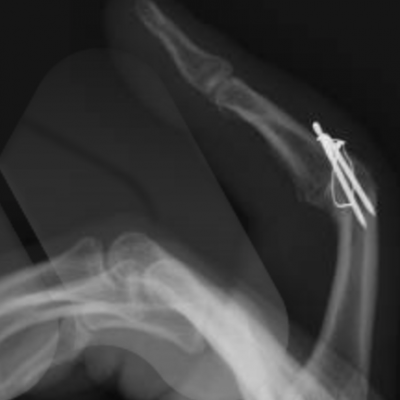

Arthrodesis

This is the technique of fusing the joint in a position of best function that is appropriate to each individual patient. This is a very durable and reliable way of relieving pain and correcting severe deformity although it does prevent any movement of the affected joint from the fused position. It has been a technique employed since the early 1900’s with good long term results. It is particularly useful in younger patients with a requirement for heavy manual activity and commonly used to treat arthritis in the smaller joints of the fingers such as the DIP joints but can be performed in almost any joint. Risks of surgery include a failure to fuse the joint causing ongoing pain, risk of implant breakage or irritation to surrounding tissues, injury to surrounding structures including skin, nerves, blood vessels and cells that produce the nail and can also be complicated by infection.